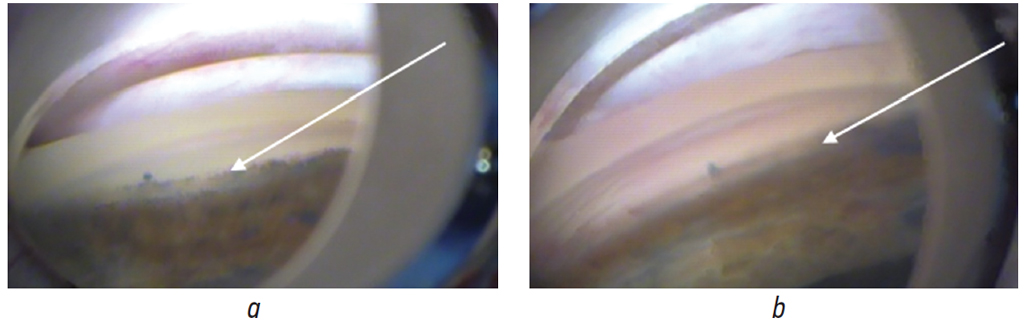

Patients of the main group underwent hydrodynamic trabeculocleaning as part of the PE stage. The irrigation–aspiration tips of the Centurion Vision System phacosystem with two external holes with a diameter of 0.3 mm were used, with the vacuum in the system of 500 mm Hg and an aspiration flow of 30 cm3/min. Under intraoperative goniolens, a balanced saline solution was supplied along the perimeter of the anterior chamber angle (360°), and debris (pseudoexfoliative material and pigment granules) was washed out (Fig. 1). Manipulation was performed after aspiration of the lens masses and before IOL implantation. Moreover, the position of the tips within the anterior chamber was monitored, and it was necessary to pass the irrigation and aspiration tips close to each other and from the trabecula, without touching the trabecula and the iris root to avoid traumatizing the tissue. The irrigation supply created a hydrodynamic impact, releasing the debris from the angle of the anterior chamber and trabecular fissures, and the aspiration part of the system immediately collected it.

Fig. 1. Trabeculocleaning under the goniolens control: a – intraoperative goniolens; b – control of trabeculocleaning / Рис. 1. Трабекулоклининг под контролем гониолинзы: a — интраоперационная гониолинза; b — контроль трабекулоклининга

Fig. 2. Fragment of a gonioscopic image in patient K., 65 years old, under conditions of intraoperative staining: a – before trabeculocleaning (the arrow points at stained pseudoexfoliative material on the trabeculum); b – after trabeculocleaning (the arrow points at the state of the tradculum) / Рис. 2. Фрагмент гониоскопической картины у пациента К., 65 лет, в условиях интраоперационного окрашивания: а — до трабекулоклинига (стрелка указывает на окрашенный псевдоэксфолиативный материал на трабекуле); b — после трабекулоклининга (стрелка указывает на состояние трабекулы)